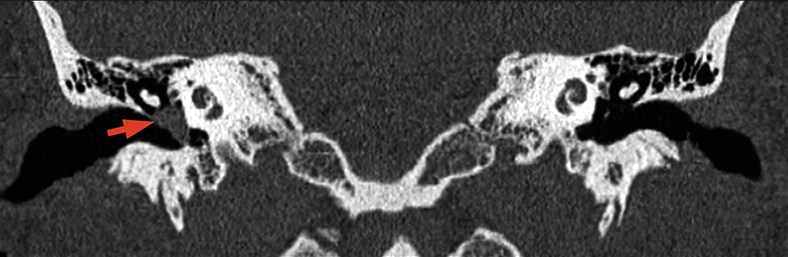

Eίναι καλοήθεις, τοπικά διηθητικοί όγκοι σε νεαρούς ενήλικες που συνήθως παρουσιάζονται με ρινορραγία και ρινική απόφραξη. Eξορμώνται από το σφηνουπερώιο τρήμα. Έχουν ευρεία βάση στα υποκείμενα οστά, χωρίς να τα διαβρώνουν.

Επεκτείνονται υποβλεννογόνια προς τα γειτονικά διαστήματα με κατεύθυνση:

- εκτός, διά του σφηνουπερώιου τρήματος στον υποκροτάφιο βόθρο και διά της υποκογχίου σχισμής προς τον οφθαλμικό κόγχο,

- προσθιοπλάγια, προς την πτερυγογναθιαία σχισμή και το ιγμόρειο άντρο.